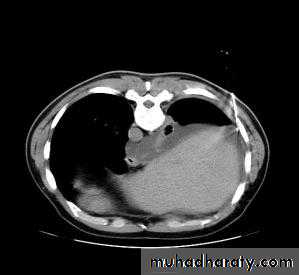

CT SCAN OF THE CHESTThoracentesis

If clinical and radiological diagnosis is not possibleDefinitive contrendication?